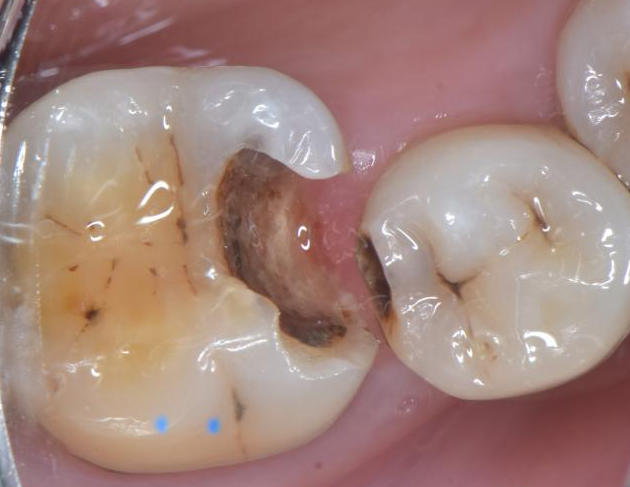

上障去龋,发现龋深近髓,慢速去龋.

step 1 去龋,备洞 去龋备洞后发现已经近髓,患者出现明显的冷刺激痛和